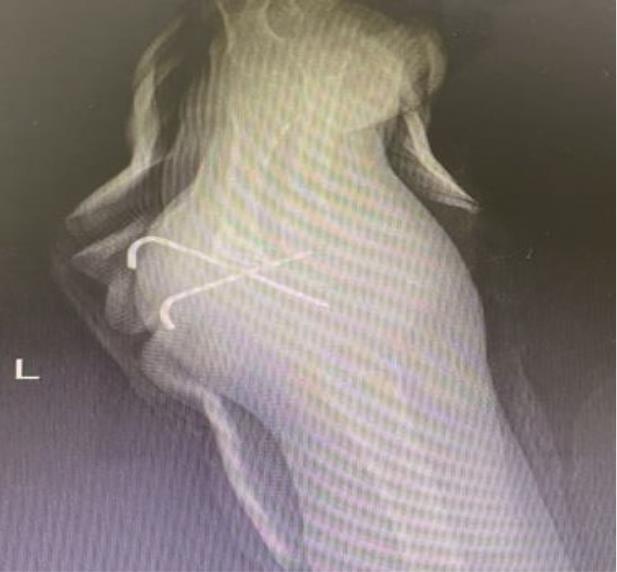

• 3D打印下精准截骨术治疗先天性尺桡关节脱位1例报道

2023, 48(5):618-620. DOI: 10.13406/j.cnki.cyxb.003218

摘要 (98) HTML (49) PDF 4.15 M (219) 评论 (0) 收藏

摘要: